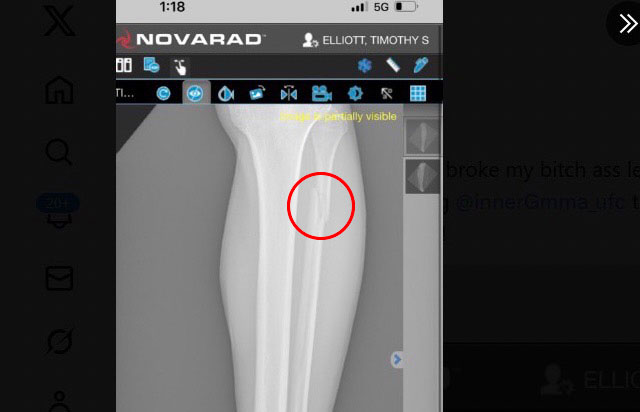

すねがポッキリと折れている(@TElliott125より)